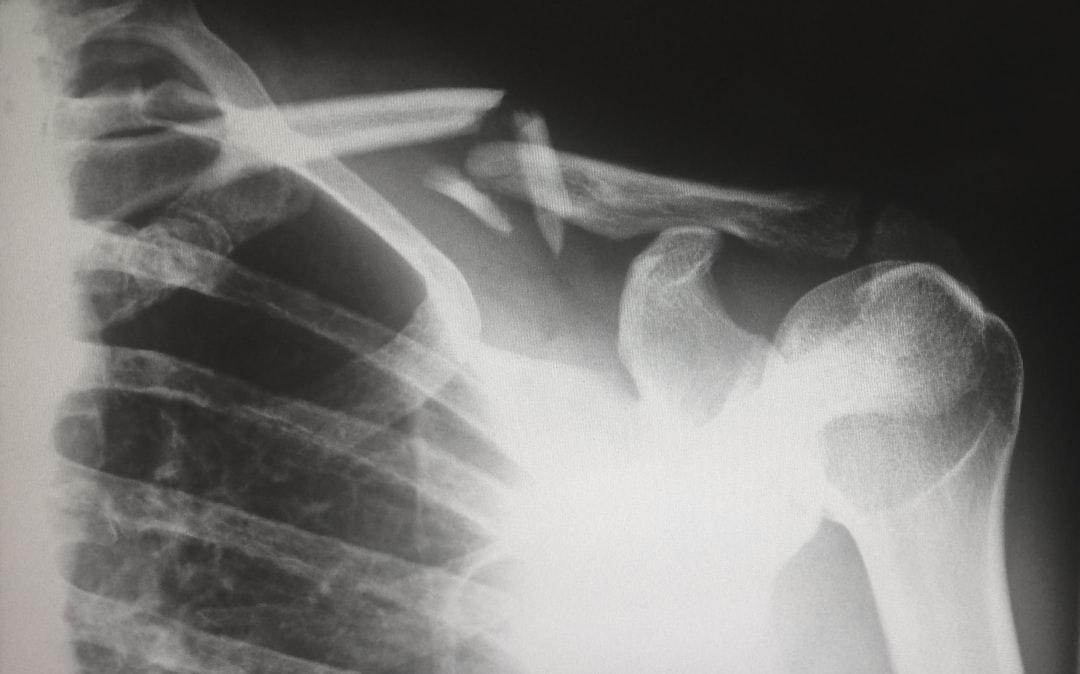

Un dolore alla spalla che non passa, la fatica nei movimenti quotidiani o quello “scatto” fastidioso ogni volta che si alza il braccio: sono alcuni segnali tipici delle lesioni alla cuffia dei rotatori, un insieme di tendini e muscoli che garantisce alla spalla la sua piena mobilità. Secondo la Società Italiana di Ortopedia e Traumatologia (SIOT), in Italia circa il 30% degli over 60 presenta lesioni o rotture della cuffia, con un’incidenza in crescita anche tra i più giovani, soprattutto sportivi e lavoratori che compiono gesti ripetitivi o usuranti. “Non si tratta solo di un problema legato all’età”, spiega la Dott.ssa Erika Viola, Consigliere SIOT e Direttore UOC Ortopedia e Traumatologia, ASST Cremona. “La cuffia può indebolirsi progressivamente per effetto del tempo, del fumo o di posture scorrette, ma anche per traumi improvvisi come cadute o movimenti errati. Alcuni sport praticati senza la giusta preparazione aumentano il rischio, così come una predisposizione familiare. Non sempre serve ricorrere alla chirurgia, ma è fondamentale riconoscere i segnali d’allarme e rivolgersi allo specialista”.

I sintomi da non ignorare sono dolore, soprattutto notturno o nei movimenti sopra la testa, debolezza, limitazione funzionale e sensazioni di “scatto” o “schiocco”. “Le lesioni possono essere molto dolorose e non sempre la gravità dei sintomi corrisponde a ciò che si osserva agli esami”, aggiunge l’esperta. “Per questo la diagnosi richiede una valutazione clinica attenta”. Nei casi più lievi possono bastare fisioterapia e infiltrazioni mirate, mentre la chirurgia, di solito artroscopica, è indicata per dolori persistenti e perdita significativa di forza. “In pazienti selezionati”, spiega il Prof. Pietro Simone Randelli, Presidente SIOT “l’intervento consente di tornare a una vita sportiva e a una spalla funzionale, anche se i tempi di recupero possono essere lunghi”. Anche fattori come diabete, obesità, ipertensione o fumo influiscono negativamente sia sulla salute dei tendini sia sulla guarigione postoperatoria, aumentando il rischio di recidive.